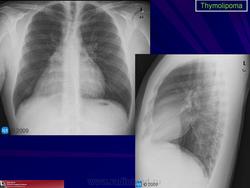

Тимолипома. Как подойти к диагностике? Судя по представленным снимкам, если neo преимущественно жировой структуры локализуется типично для тимомы в переневерхнем средостении + протяженность, объем neo большие и neo выглядит цельным образованием, не составляющими-фрагментами.